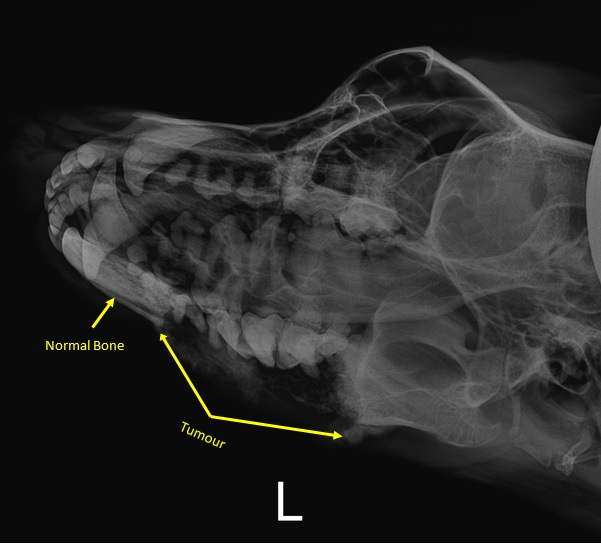

• Follow Roxy's Bone Cancer Journey

• Xray

Xray